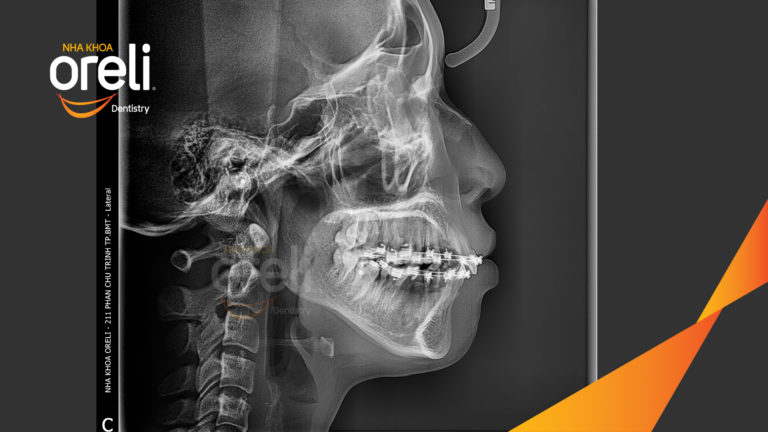

Ca chỉnh hô có nhổ 4 răng 4 thay đổi góc nghiêng đẹp – Kết quả thay đổi sau 3 năm tại nha khoa Oreli Niềng răngHô Xem thêm

Ca niềng chỉnh hô nhổ 2 răng 4 hàm trên di gần răng 7 8 hàm dưới cho nụ cười đẹp – Kết quả sau hơn 2 năm ở Oreli Niềng răngDi gần răng 7 8Hô Xem thêm